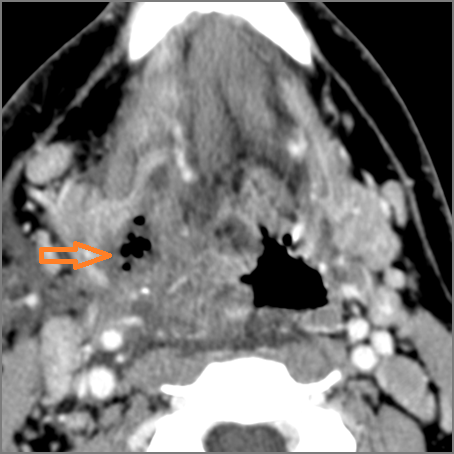

9 month old male presenting to the emergency room with poor feeding, fever, respiratory distress and possible retropharyngeal abscess or suppurative retropharyngeal adenitis.Exam

There is excessive enhancement or thickening of the mucosa or hypertrophy of the palatine or lingual tonsillar tissue or the lymphoid tissue along the glossotonsillar sulci and posterior pharyngeal wall. |

Yes | NA |

There is reactive retropharyngeal lymphadenopathy. |

There is suppurative retropharyngeal lymphadenopathy. |

Pharyngitis with suppurative retropharyngeal adenitis.